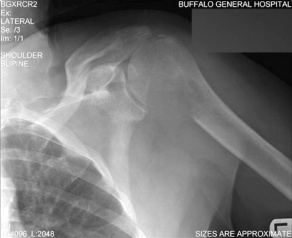

Renal Cell Carcinoma Metastasis